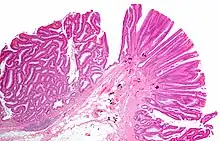

| Tubulovillous adenoma (tubular component – left of image, villous component – right of image). H&E stain. | |

Tubulovillous adenoma

Tubulovillous adenoma, TVA are considered to have a higher risk of becoming malignant (cancerous) than tubular adenomas.[9]